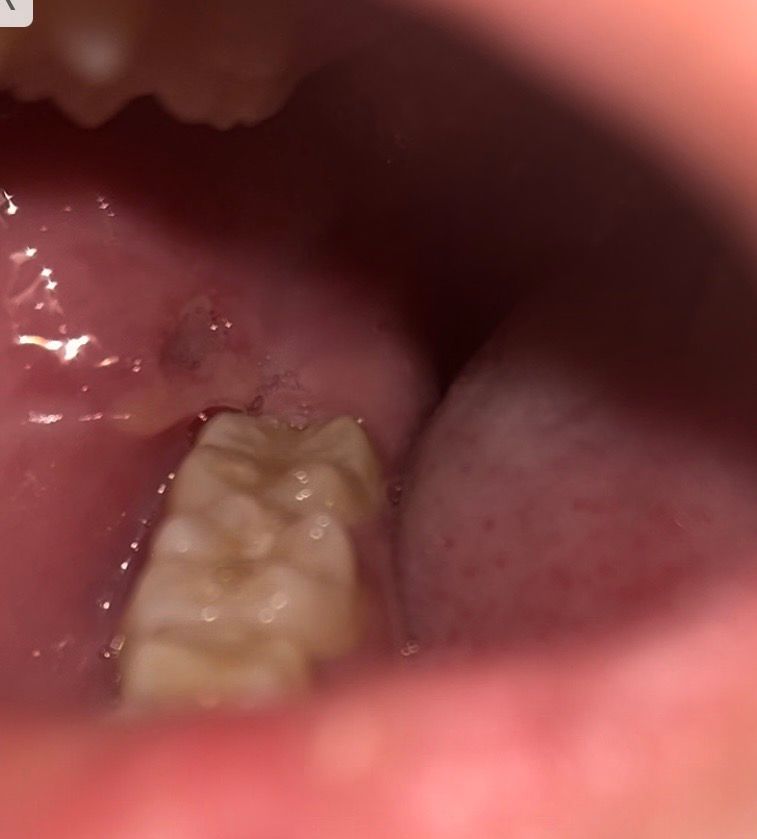

요즘 공부하느라 잠 많이 못 자서 그런지 아니면 깨물었던 건지 구내염이 생겼네요 찾아봤는데 편평태선 이라는 것도 있더라고요 혀 옆면에 붉은 반점 같은게 저렇게 있는데 맞나요? 뭐죠 저게ㅜ 어릴때부터 있었던 거 같아요 또 그냥 구강 상태 괜찮은건가요 20대 초반 흡연자입니다ㅜ 걱정되네요

• 3번 째 사진